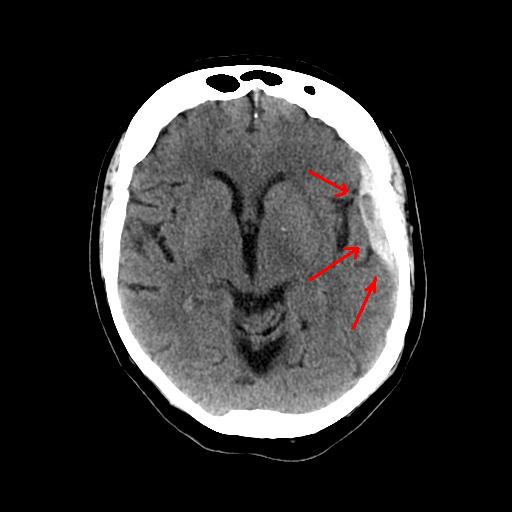

경막하 혈종의 CT 이미지 (출처 : 위키미디어)

또 다른 치매 증상을 보이는 질병에는 만성 경막하 혈종이 있습니다. 외상 등에 의해 뇌를 둘러싸고 있는 막중 하나인 경막에 서서히 피가 차게 되어 뇌를 압박하여 마치 치매 증상이 나타나듯이 서서히 인지장애나 신경학적 이상 등이 나타나게 되는 것입니다. 만성 음주자이신 분들(자신도 기억 못하는 머리 손상이 많이 발생하기 때문)이 갑자기 치매 증상을 보이는 경우가 바로 만성 경막하 혈종에 의한 치매 증상인 것입니다. 이 또한 수술을 통해 경막 아래에 찬 혈액을 제거해 주면 인지장애나 신경학적 이상 등이 호전될 수 있습니다.